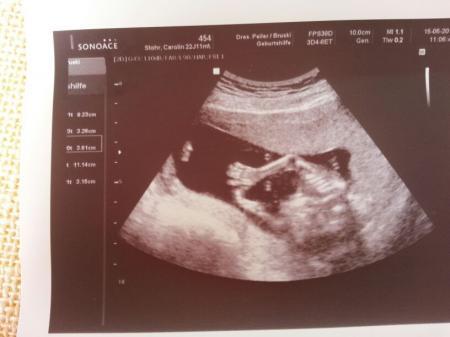

achja auf dem ersten bild direkt zwischen den beinen ;) hier einmal von schäh oben das händchen

Bild zu